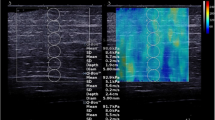

Figure 2 shows the time evolution of the ultrasonic pulses (US) as a function of the temperature for the heating stage of the second cycle. As the sample of muscle tissue increases (decreases) its temperature the US presents a temporary shift and change in amplitude.

To analyze the evolution of the attenuation, the behavior of the maximum of the amplitude spectrum is followed (Fig. 3).